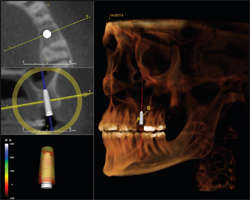

If desired, the doctor can use the captured 3-D data in other 3-D imaging implant programs. As seen here with i-CAT scan data in InVivioDental's™ Anatomage, the dentist can use the many tools found in the program, including virtual placement of the implant (Fig. 3).

Current advancements also allow clinicians to plan the restorative phase using CBCT scans in 3-D imaging programs, seen here with Anatomage (Fig. 4).